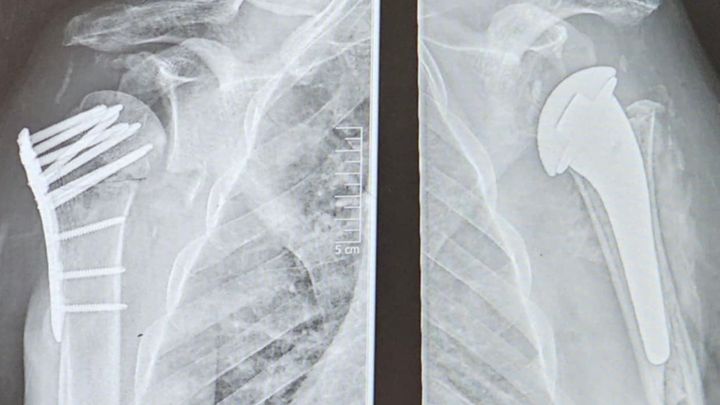

Hi, my name is Pete, and I am reaching out on behalf of my best friend, Michael, who is going through an incredibly tough time. In April, Michael suffered a devastating injury, breaking both of his shoulders. Since then, he has endured four surgeries to repair the damage, but his journey has been far from smooth. The work done on his right shoulder has failed—the bone is no longer viable and is essentially dead. Now, he is facing a complex fifth surgery on December 9 to remove and replace the damaged bone entirely. Michael has been unable to work since his injury, making it difficult for him to support himself. Even the simplest tasks—like sweeping the floor, getting dressed, or carrying a plate—have become impossible. This situation has been emotionally, physically, and financially overwhelming for him. I’m asking for your help to support Michael as he fights to regain his independence and quality of life. Your contributions will go directly toward his medical expenses, daily living costs, and the resources he needs during his long recovery process.